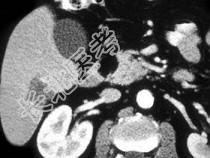

- 单项选择题结合图像,该胰腺团块, 最不可能的诊断为 ( )

A、肉瘤

B、脂肪瘤

C、胰腺囊肿

D、以上都有可能

E、以上都不是